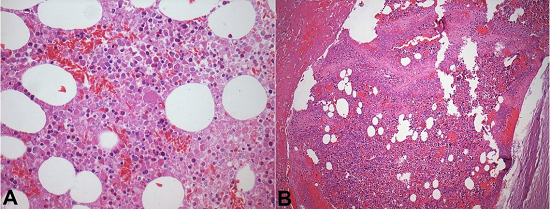

The lungs were edematous and boggy with multiple areas of friable consolidation and gross thromboemboli (Figure 3).

Microscopic examination showed acute and organizing thrombi, and mainly necrotic bone marrow embolism in pulmonary artery branches and arterioles, fat embolism in the alveolar septa capillary, and fibrin thrombi. There were multifocal areas of pulmonary congestion, hemorrhage, alveolar edema, and diffuse alveolar damage (Figure 4). Focal hemosiderin deposition was a sign of previous chronic hemorrhage.

The bone marrow was hypercellular, mainly due to precursor erythroid cell hyperplasia, with large areas of infarction (about 50%), hemorrhage, and sickled cells (Figure 5).